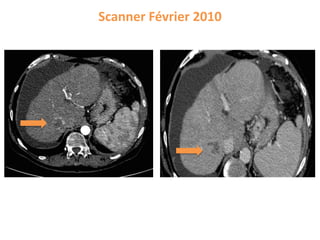

Bilan pré-transplantation hépatiqueScore αFP = 2

Scanner Février 2010